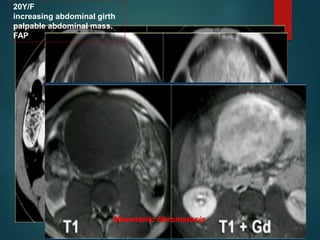

20Y/F

increasing abdominal girth

palpable abdominal mass.

FAP

Mesenteric fibromatosis

Mesenteric fibromatosis – •Also known as intra-abdominal fibromatosis/ abdominal desmoid / desmoid tumor. • Benign proliferative process that is locally aggressive ,does not metastasize. • MC site …small bowel mesentery • May associate FAP.

20Y/F increasing abdominal girth palpableabdominal mass. FAP Mesenteric fibromatosis

• #42 Ct…well circumscribed lesion with low density.there is some enhancement around the lesion and some strands of enhancement within the lesion. On MR there is low signal on t1 and t2 high signal.in combination with low density on ct this tells us there is mucin within the lesion. …finding suggestive of diagnosis of mesenteric fibromatosis.enhancement on MR is more intense compared to the enhancement on ct. On the CT the low density of the mucin stands out but on mr we can appreciate the enhancement better,it tell us the lesion is well vascularised.